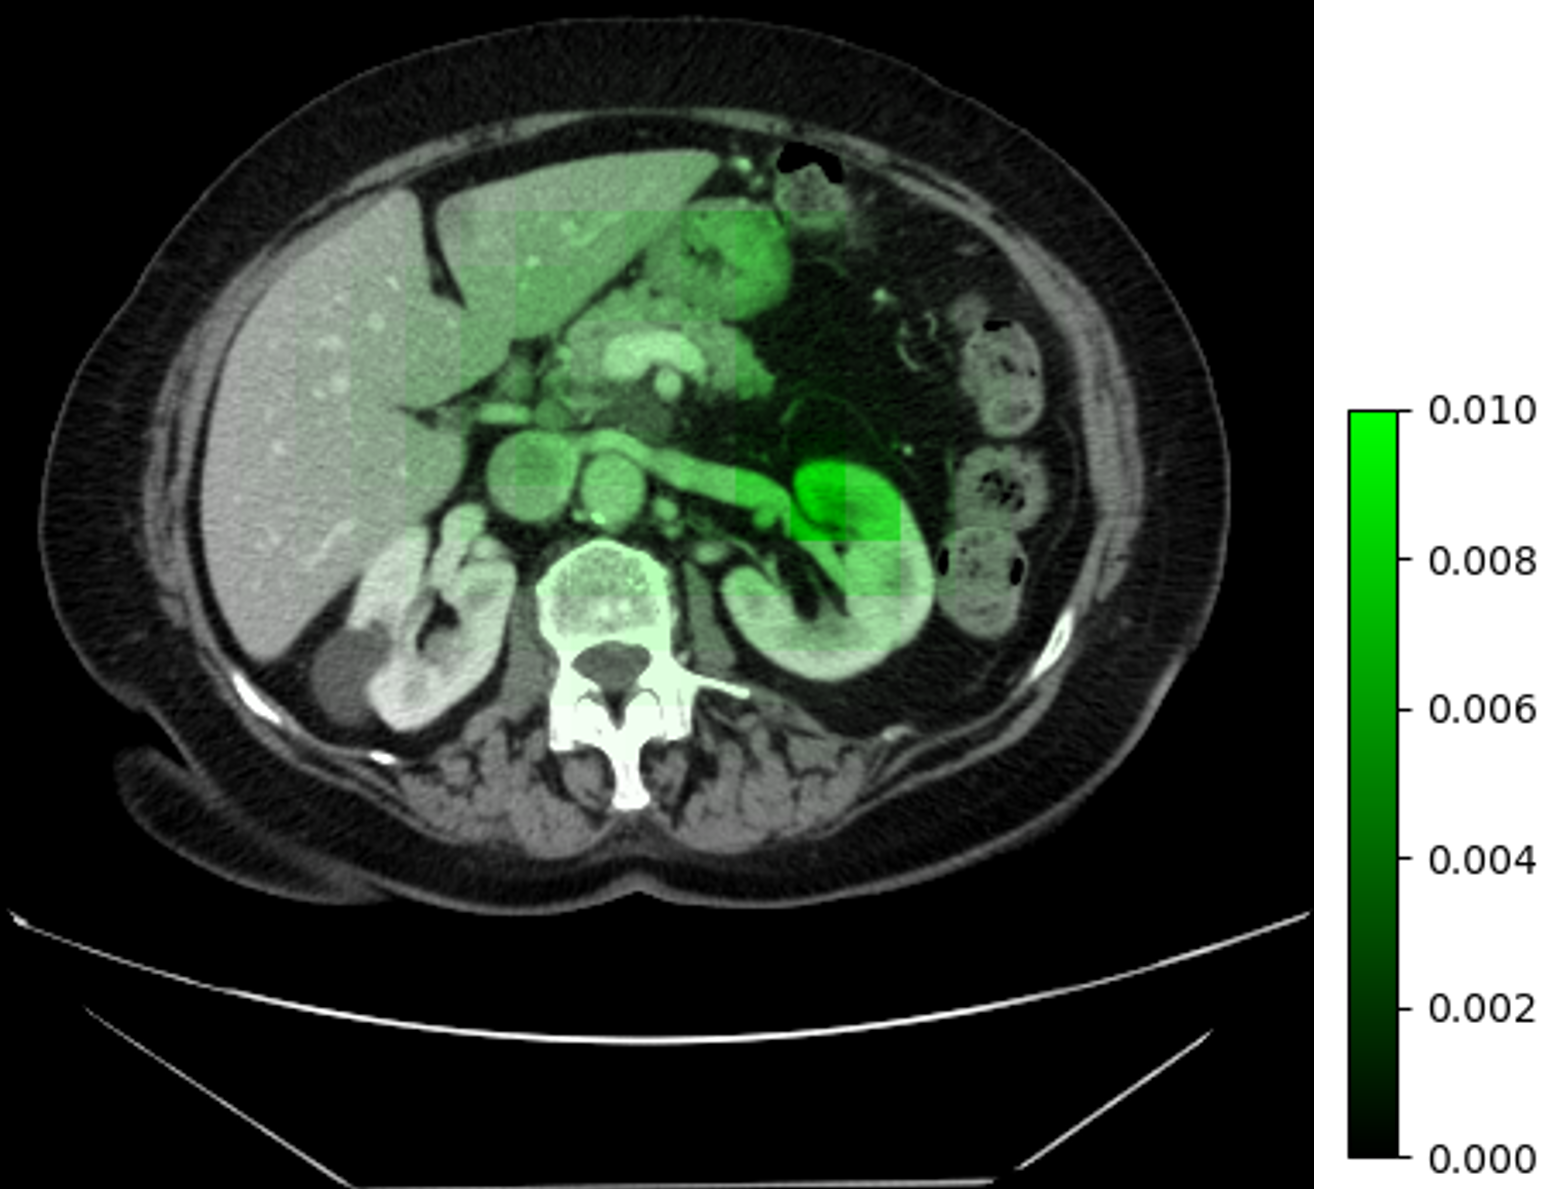

Refer to caption

(a) Δωθa(I)Δsubscriptsuperscript𝜔𝑎subscript𝜃𝐼\Delta\omega^{a}_{\mathcal{H}_{\theta}}(I) and labels

(b) ΔωθI(ai,aj)Δsubscriptsuperscript𝜔𝐼subscript𝜃subscript𝑎𝑖subscript𝑎𝑗\Delta\omega^{I}_{\mathcal{H}_{\theta}}(a_{i},a_{j})

Figure 6: Visualization of changing ωθa,Isubscriptsuperscript𝜔𝑎𝐼subscript𝜃\omega^{a,I}_{\mathcal{H}_{\theta}} depends on different image or architecture inputs. We use our 5GB and 7GB architectures as aisubscript𝑎𝑖a_{i} and ajsubscript𝑎𝑗a_{j} in 6(b). Results are aggregated based on sliding-window averaging with a stride size of sixteen.

HyperNet Analysis. We provide some insights into the behavior of the HyperNet \mathcal{H} and its output ωθa,Isubscriptsuperscript𝜔𝑎𝐼subscript𝜃\omega^{a,I}_{\mathcal{H}_{\theta}}. While it is difficult to interpret the channel-wise weights individually, we can observe how ωθa,Isubscriptsuperscript𝜔𝑎𝐼subscript𝜃\omega^{a,I}_{\mathcal{H}_{\theta}} changes with different inputs. To do so, we fix the architecture vector larchsubscript𝑙archl_{\textrm{arch}} and provide \mathcal{H} with limagesubscript𝑙imagel_{\textrm{image}} generated from different patches. Similarly, we can fix limagesubscript𝑙imagel_{\textrm{image}} and change larchsubscript𝑙archl_{\textrm{arch}} to observe the differences based on architectures. We observe that the majority of the patches yields very similar ωθa,Isubscriptsuperscript𝜔𝑎𝐼subscript𝜃\omega^{a,I}_{\mathcal{H}_{\theta}}, while a few patches have very different weights. To quantify, we define two metric:

where Δωθa(I)Δsubscriptsuperscript𝜔𝑎subscript𝜃𝐼\Delta\omega^{a}_{\mathcal{H}_{\theta}}(I) measures the 2subscript2\mathcal{L}_{2} distance between ωa,Isubscriptsuperscript𝜔𝑎𝐼\omega^{a,I}_{\mathcal{H}}, which is from a specific patch I𝐼I, and ω¯asubscriptsuperscript¯𝜔𝑎\overline{\omega}^{a}_{\mathcal{H}}, which is the average weights over all patches in a given volume; ΔωθI(ai,aj)Δsubscriptsuperscript𝜔𝐼subscript𝜃subscript𝑎𝑖subscript𝑎𝑗\Delta\omega^{I}_{\mathcal{H}_{\theta}}(a_{i},a_{j}) measures the difference between weights generated from architecture aisubscript𝑎𝑖a_{i} and ajsubscript𝑎𝑗a_{j} on the same patch.

We visualize these two metrics on a sample CT volume in Fig. 6, along with the segmentation labels. For patches that are not relevant to the labels, \mathcal{H} generates very similar ωθa,Isubscriptsuperscript𝜔𝑎𝐼subscript𝜃\omega^{a,I}_{\mathcal{H}_{\theta}}; on the other hand, patches that contain labels yield significantly different weights. Furthermore, ΔωθI(ai,aj)Δsubscriptsuperscript𝜔𝐼subscript𝜃subscript𝑎𝑖subscript𝑎𝑗\Delta\omega^{I}_{\mathcal{H}_{\theta}}(a_{i},a_{j}) is also significant on foreground patches, and minimum on background patches. This suggests that \mathcal{M} and \mathcal{H} implicitly partitions potential foreground regions, which is a strategy similar to foreground oversampling used in methods like nnU-Net [19]. While our method does not employ explicit foreground oversampling, the HyperNet design appears to automate such a strategy. For more details on the visualization of ωθa,Isubscriptsuperscript𝜔𝑎𝐼subscript𝜃\omega^{a,I}_{\mathcal{H}_{\theta}}, please refer to the Supplemental Material.